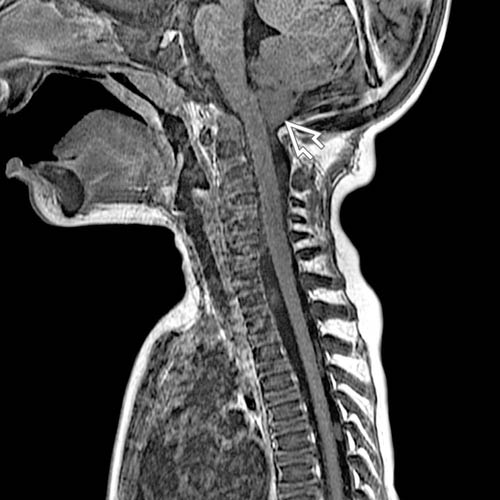

Figure 1 from Osteopetrosis (Marble Bone Disease) A Rare Disease in What Is Marble Bone Disease Osteopetrosis is group of a rare disorders that cause bones to grow abnormally and become overly dense. In addition, bones may be misshapen and large, causing other problems in the body. The disease progresses as long as bone growth. Osteopetrosis is a group of rare disorders that cause bones to grow abnormally and become too dense. Osteopetrosis, or marble bone. What Is Marble Bone Disease.

Figure 3 from Osteopetrosis (Marble Bone Disease) A Rare Disease in What Is Marble Bone Disease Marble bone disease, rare disorder in which the bones become extremely dense, hard, and brittle. Osteopetrosis is a condition in which abnormal bone growth and high bone density can lead to a vulnerability to bone fractures and other effects, such as bleeding. The disorder may be mild to. When this happens, bones can break easily. Osteopetrosis is a group of. What Is Marble Bone Disease.